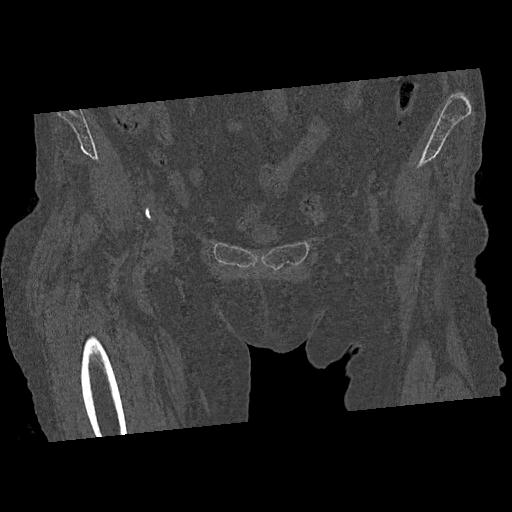

110286 2/17 股関節 2R 74歳女性 右人工骨頭

102903 股関節 2R 1/28 +股関節 2R 1/29 78歳女性 左人工骨頭

100703 1/27 両股正面+軸 1/29 両股正面+軸 94歳女性 パンソンロン

46666 1/28 両股正面+軸と 1/26 右手関節 2R 76歳女性 右転子部骨折

37 1/18 両股正面+軸 1/22 2R 86歳女性 右転子下

82084 1/14 1/20 股関節 2R 78歳男性 右人工骨頭

102811 1/13 股関節 2R 1/19 2R 80歳女性 右DHS

91569 3/25 両股正面とラウエン 70歳女性 人工骨頭+バンクーバー